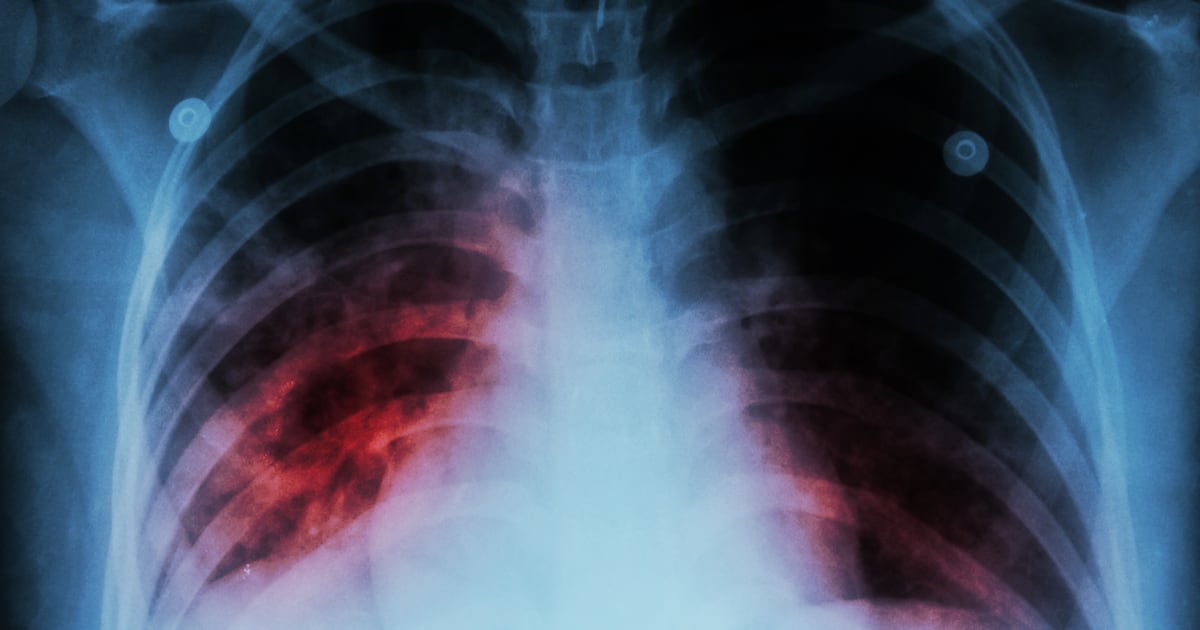

Tuberculosis is a contagious bacterial respiratory infection that primarily targets the lungs but can also affect the brain, kidneys and spine. According to the Centers for Disease Control and Prevention, cases of the disease have been rising nationally since 2021.

Health officials said the bacteria spreads through the air when an infected person coughs or laughs. While not everyone who is infected becomes sick, treatment is required to prevent them from transmitting the infection to others. Routine screenings are recommended for residents at higher risk or those who require testing for school or employment.